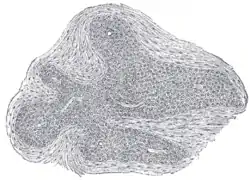

Section of an irregular nodule of the glomus coccygeum. X 85. The section shows the fibrous covering of the nodule, the bloodvessels within it, and the epithelial cells of which it is constituted. | |

It is about 2.5 mm. in diameter and is irregularly oval in shape; several smaller nodules are found around or near the main mass.

It consists of irregular masses of round or polyhedral cells epitheloid cells, which are grouped around a dilated sinusoidal capillary vessel.